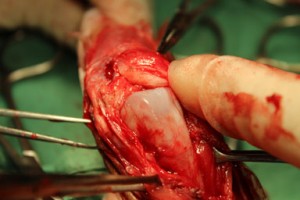

膝蓋骨が上に乗る滑車溝にまったく溝がなく、つるつるの状態でした。これでは膝蓋骨は脱臼してしまいます。